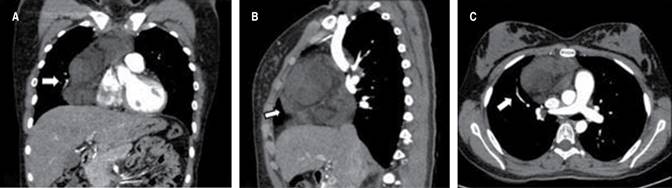

A 15-year-old adolescent with a history of cutaneous lupus was admitted with a five-month evolution of asthenia, adynamia, dyspnea on medium efforts and pleuritic chest pain in the right hemithorax, without B symptom. In the study of dyspnea, a contrasted chest computed tomography (CT) was performed: anterior mediastinal mass of 124 × 90 × 87 mm with various areas of soft tissue density and fatty tissue elements, extending posteriorly until compromising the mediastinal fat of the junction between the superior mediastinum and inferior, in contact, without infiltrating the walls of the left venous brachiocephalic trunk, the arch of the azygos vein, the right brachiocephalic artery, the dorsal and middle ventral aspect of the superior vena cava as well as the ventral aspect of the ascending segment of the aorta a level of the arch and the right anterior and medial aspect of the pulmonary artery infundibulum and exerting extrinsic compression without infiltration of the wall at the level of the right atrium, without evidence of metastatic lesions (Figure 1). A biopsy was performed by mediastinoscopy that reports myxoid liposarcoma without a round cell component.

Figure 1: Contrast-enhanced chest computed tomography. Arrow points the mass in anterior mediastinum. A) Coronal plane, B) sagittal plane, C) axial plane.